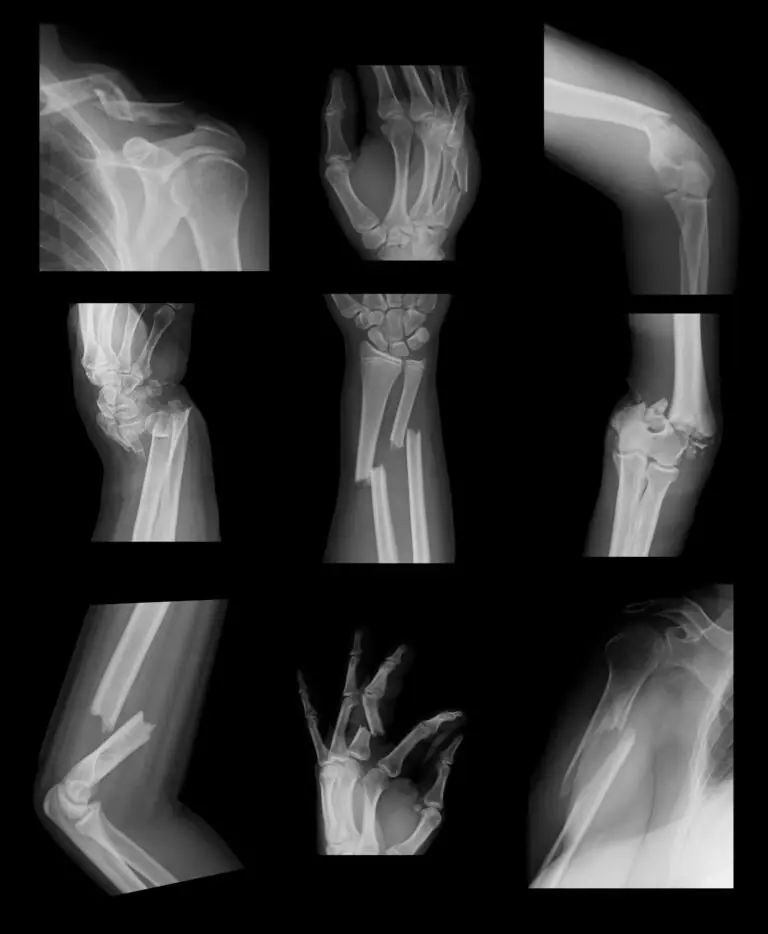

C) Radiological (according to the configuration of the fracture

or

according to direction of force/Shape of fracture):

1. Transverse fracture – by angulations force. (An angle <30 degreee with horizontal line)

2. Oblique fracture – by twisting force. (An angle 30 Degree with horizontal line)

3. Spiral fracture – by twisting force.

4. Z-fracture by angulations plus resistance force.

5. Comminuted fracture – more than two fragments by angulations force or crushing force or direct force. Bone is broken in several place.

6. Wedge fracture – in vertebral body by vertical force.

7. Avulsion fracture – a small fracture fragment in pulled and shifted by the attached muscle, e.g. fracture epicondyle.

8. Depressed fracture – by direct violence e.g. skull bone.

9. Impacted fracture – by the force along the axis of bone, The end of the bone are pushed into one another. e.g. fracture neck.

10. Burst or shattered fracture – multiple small fragment, separation. In spongy bone e.g. body of vertebra, patella, talus and calcaneous.

Confirmation the diagnosis of fracture:

A) Special investigations :

1) X-ray: Commonly used.